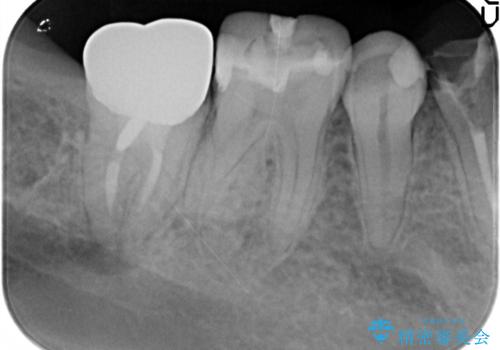

- 過去、多数の部位の虫歯治療を受けこれまで再発を繰り返してきたことから「徹底的な虫歯治療を受けたい。」と希望され来院されました。

虫歯の大きさから保存できなかった歯はインプラント治療を行い、その他の歯は虫歯のステージに合わせて根管治療、セラミックインレー、 セラミッククラウンを精密に行うことで長期的な予後を期待できる状態へと治療を進めます。